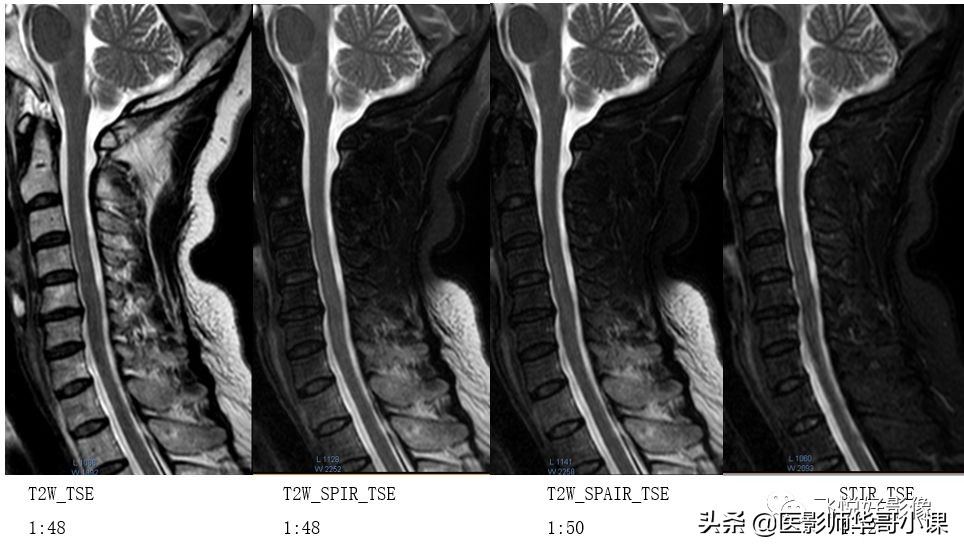

我们通过这一组图像来看看不同的脂肪技术,思考几个问题,经常使用的SPIR、SPAIR为什么在颈椎压脂“失败”了?STIR压脂那么干净为什么不使用在全身各部位,甚至增强扫描?